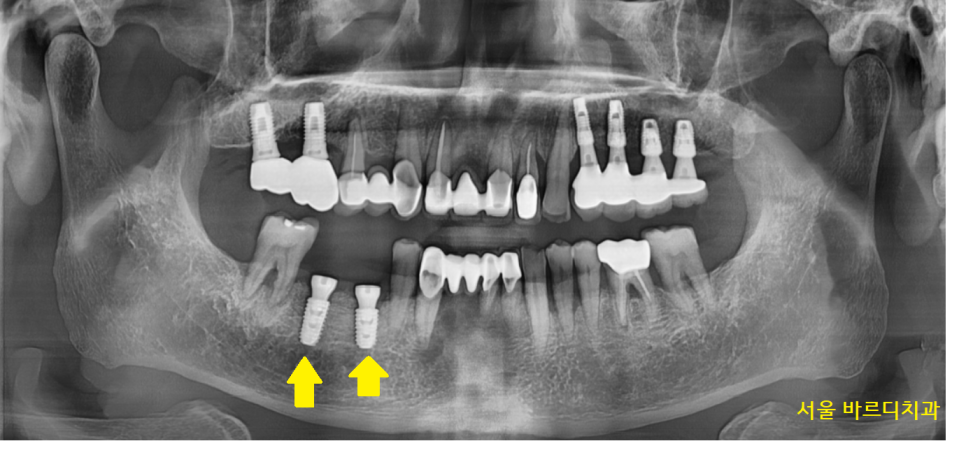

23.10.26

명일역 임플란트 수술 후 사진입니다.

심었던 임플란트도 관리가 제대로 안되면

잇몸뼈가 녹아서 오래 못쓰는데요.

움직이는 치아 관리와 함께

명일역 치과에서

계속적으로 관리해드릴게요~!!